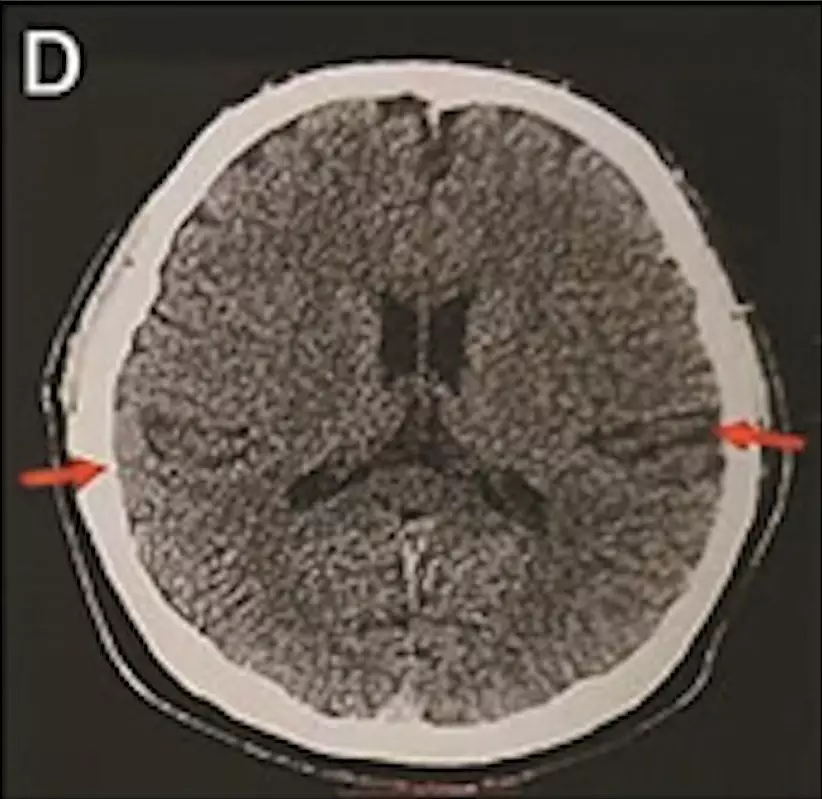

最年輕的19歲阿茲海默症男子腦部掃描結果:

該名19歲男子到醫院接受多項檢查,包括腦脊液指標檢測及正電子掃描。結果顯示,他出現輕度腦萎縮等症狀,最終被臨床診斷為「阿茲海默症」。